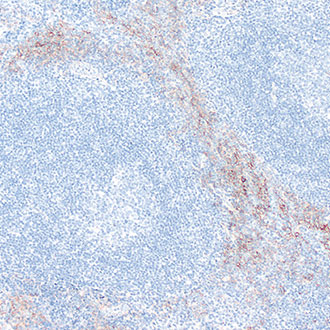

CD1a

CD1a -